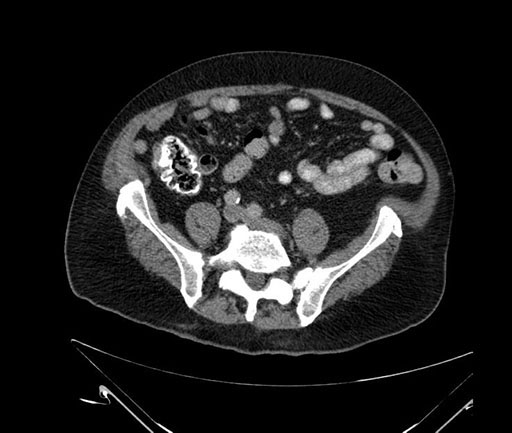

Whipple (pancreaticoduodenectomy) [case 7]

Axial - stented